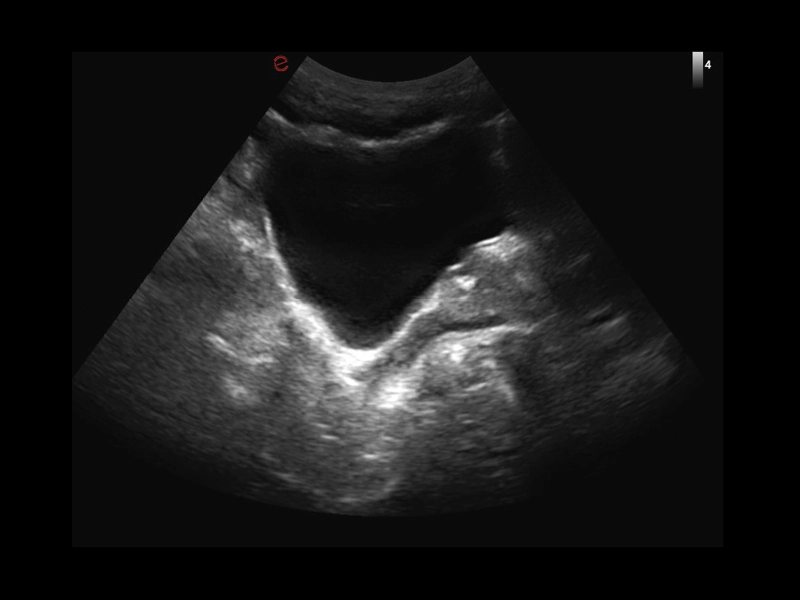

Q7 - GI Kidney

Q7 - GI Kidney